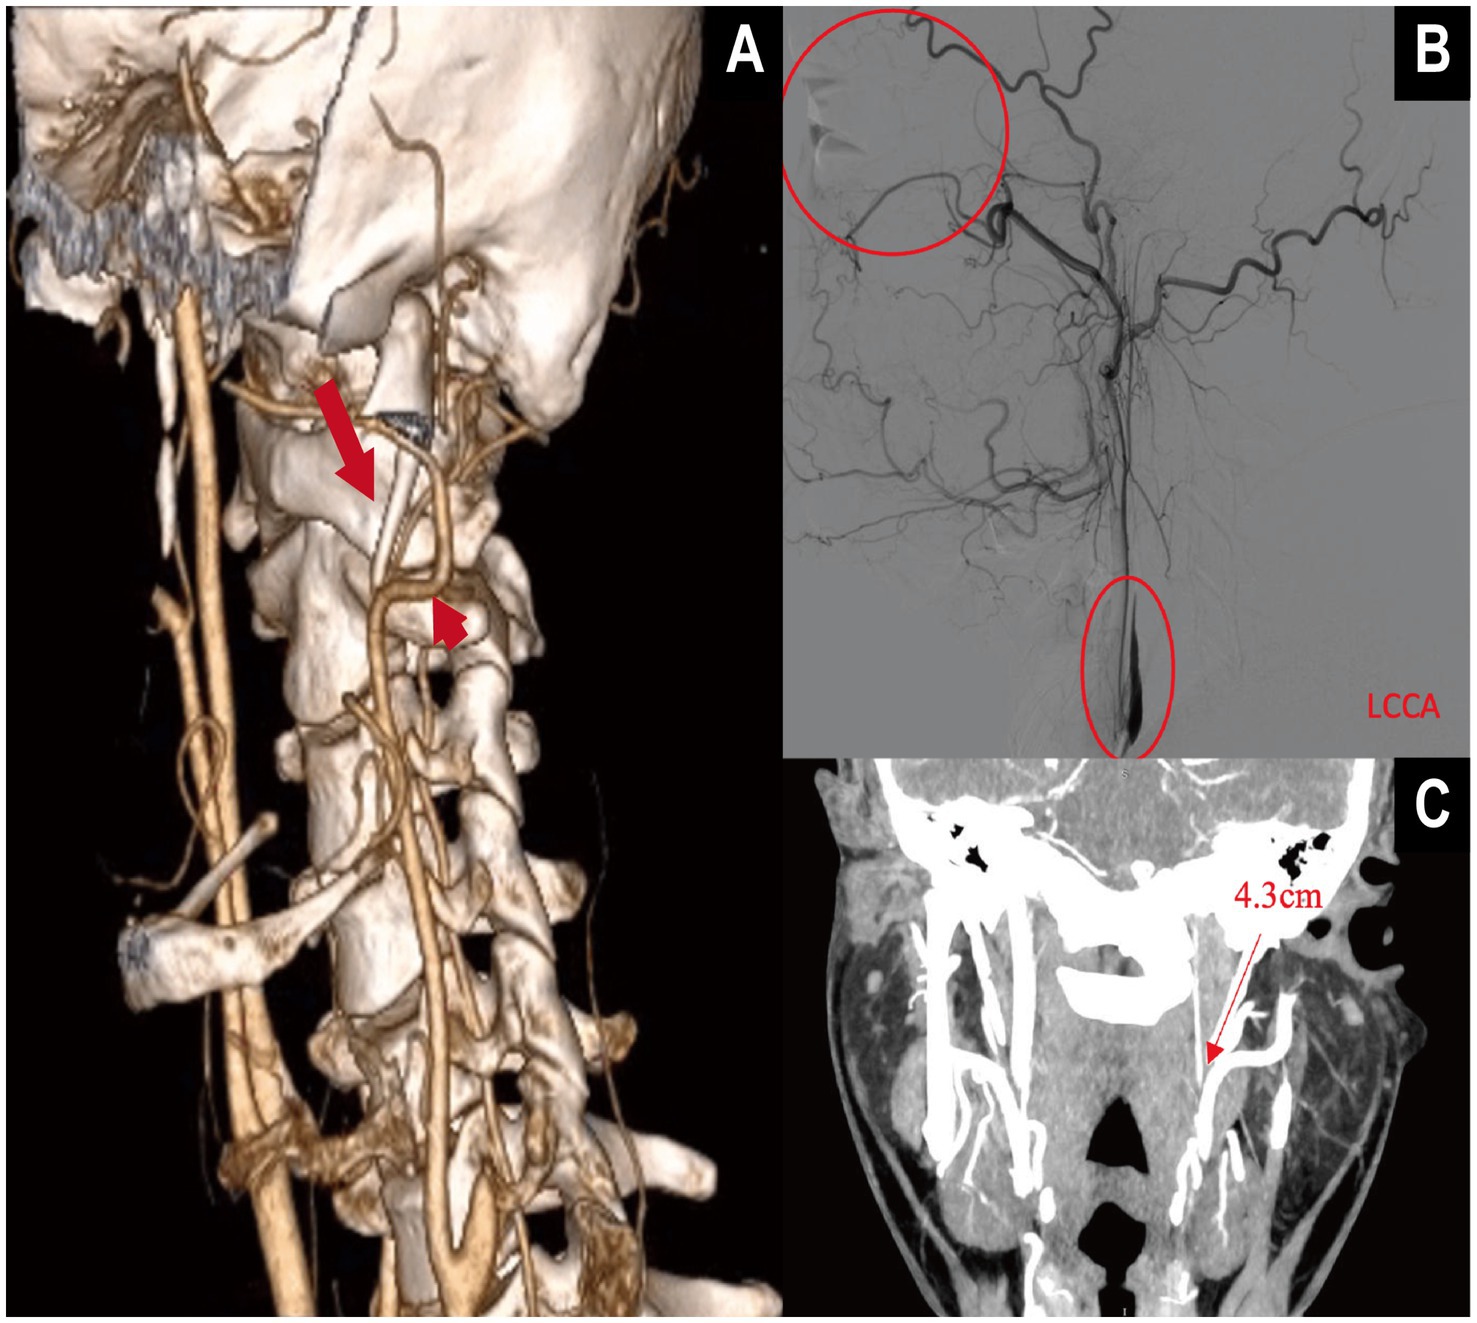

Prior work commonly used SPL >3.0 cm as an empirical threshold for elongation (7), and defined angular abnormalities using IA >15° and FTA >30° (9). However, radiographic elongation is not sufficient for ES–CA. In our series, only six patients (1.4% of the cohort; 5.4% among contact-positive cases) were diagnosed with ES–CA–related ICA dissection or stenosis leading to ischemic stroke, a clinically uncommon but easily underrecognized entity (Figure 5). This underscores the need for proactive structural risk identification. Our nomogram is expressly intended to support quantitative risk assessment in outpatient or imaging settings before overt stroke, thereby facilitating earlier recognition and individualized intervention to prevent irreversible ischemic events.

Figure 5

Multimodal imaging demonstration of internal carotid artery (ICA) dissection secondary to elongated styloid process in vascular Eagle syndrome (VES). (A) Three-dimensional CTA with volume rendering (VR) shows a markedly elongated styloid process. The long straight arrow indicates the elongated styloid process, while the short straight arrow marks the contact point with the ipsilateral internal carotid artery (ICA). (B) Digital subtraction angiography (DSA) reveals a “rat-tail” tapering deformity of the ICA, consistent with arterial dissection, without collateral reperfusion. The patient presented with central retinal artery occlusion in the left eye. (C) The VR image shows the left styloid process measuring 4.3 cm, located adjacent to the ICA, supporting the anatomical basis of compression.